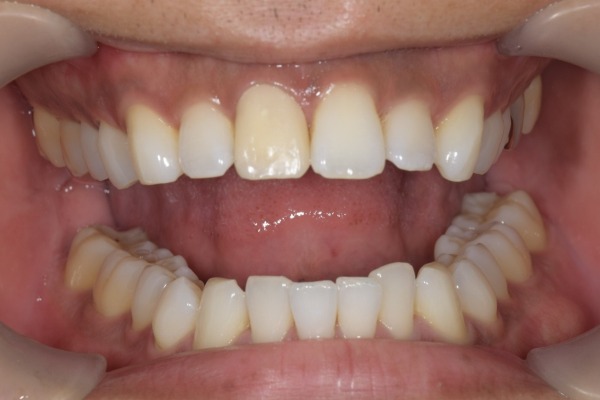

治療前の噛んだ状態の写真です。